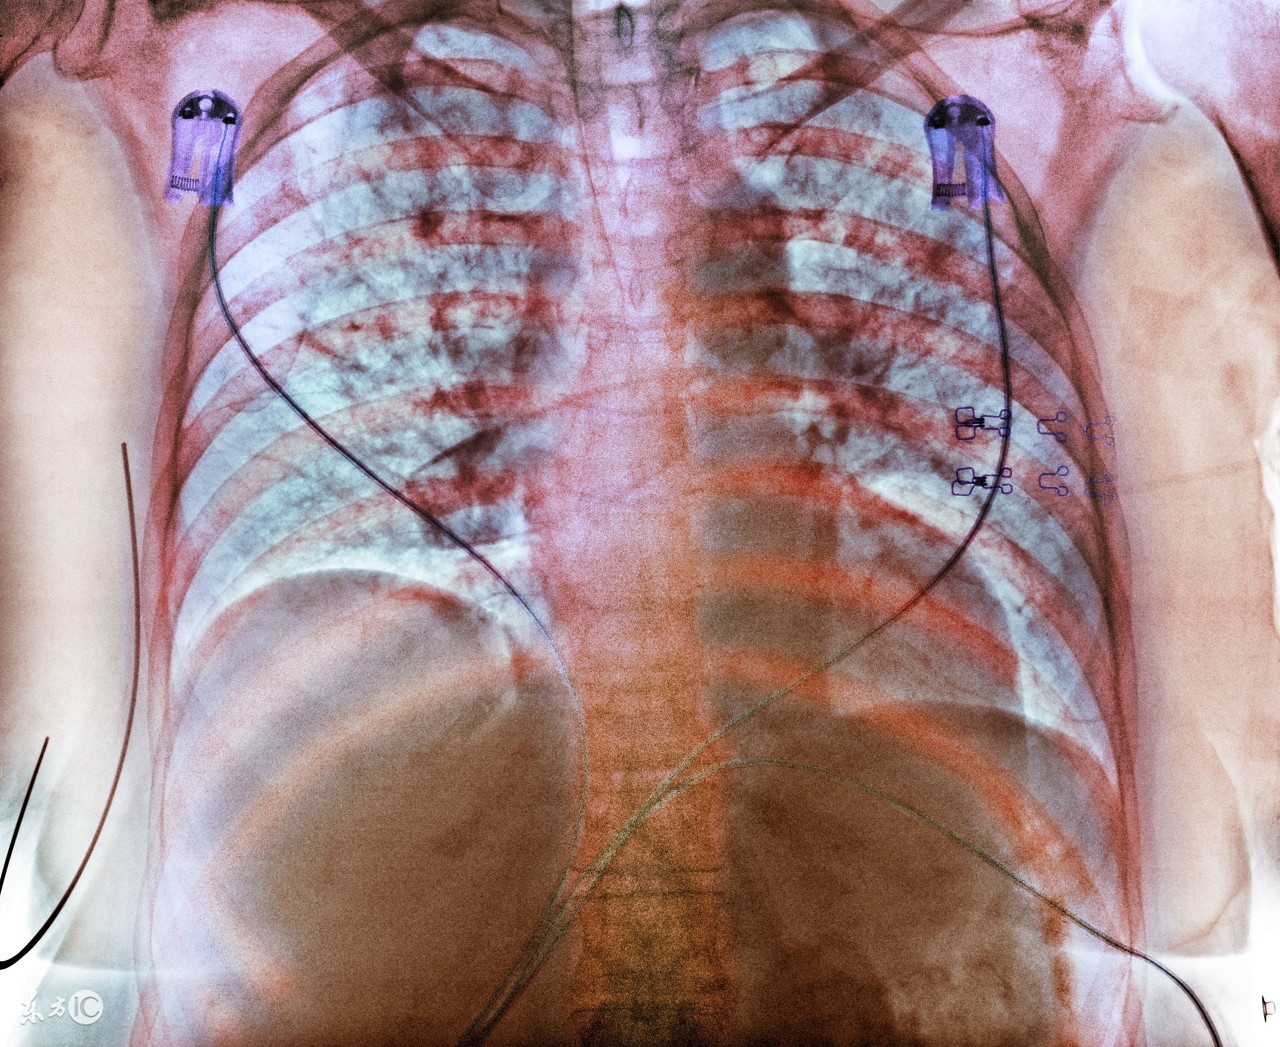

很多肺结核患者在确诊之后,就要马上接受治疗。其实,在临床上,治疗肺结核的方法有很多,很多早期的患者会选择药物治疗,严重的患者就要接受临床治疗了。那么,中医怎样治疗肺结核疾病?其实,治疗方法是根据患者的病情所决定的,中医治疗针对患者的身体损害是很小的。